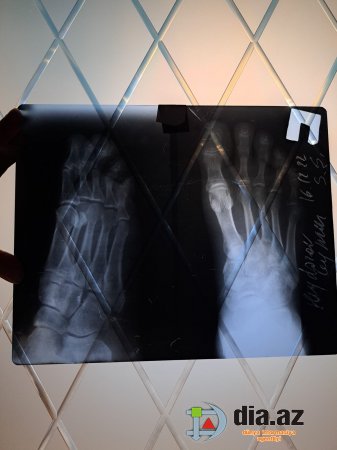

DİA.AZ: - "Şikayətim Elmi-Tədqiqat Travmatologiya və Ortopediya İnstitutunda qeyri-rəsmi çalışan rezident Ağa Mirməhəmməd Mirhaşım oğlundandır. 16.12.2022-ci il, 21:30 radələrində yoldaşım Ceyhun Heydərov avtomobil qəzası keçirmiş elə həmin gün Travmatologiya İnstitutuna müraciət etmişdir. İlkin baxış və rentgen müayinələrindən sonra özünü həkim kimi təqdim edən Ağa Mirməhəmməd rentgen nəticələrini düzgün oxuya bilməmiş və yoldaşımı arxayın edərək heç bir sınıq olmadığını, əzilmə və sıyrıq olduğunu demiş, xəstəni evə yola salmışdır". DİA.AZ bildirir ki, bu sözlər şikayətçi Gülyaz Əbilova-Heydərovanın müraciətində yer alıb. Narazı vətəndaş daha sonra bildirir: "Bir neçə gün sonra ayağın göyərdiyini və şişdiyini gördüyümüz üçün yenidən Travmatologiya İnstitutuna müraciət etmişik. Bu dəfə bir digər həkim travmatoloq 16.12.2022-ci ildə çəkilmiş elə həmin rentgen nəticələrinə baxaraq ayağın topuq nahiyəsində sınıq olduğunu aşkar etmiş. Təkrar KT müayinəsi etdirmiş və sınıq olduğunu tam dəqiqliklə təsdiqləmişdir. (Eyni zamanda tam əmin olmaq üçün özəl klinikalardan birinə də müraciət etmişik) Sınıq ilk gün Ağa Mirməhəmməd tərəfindən aşkarlanmadığı və dəqiq diaqnoz qoyulmadığı üçün sınıq yerdəyişmiş və nəticədə yoldaşım Ceyhun Heydərov 30.12.2022-ci ildə əməliyyat keçirmişdir. Əməliyyatdan bir neçə gün sonra Ceyhun Heydərov çox sakit və təmkinli bir şəkildə həmin şəxslə əlaqə saxlayıb, etdiyi səhvin nəticələrini özünə bildirmək istəyərkən şəxs-Ağa Mirməhəmməd Mirhaşım oğlu həkim peşəsinə və insanlığa sığmayan ifadələr işlədərək xəstəni təhqir edir, hədələyir, videodan da gördüyünüz kimi kriminal avtoritet kimi danışır, xəstəni və yaxınlarını "görüş"ə dəvət edir. Zərərçəkmişə "Sənin əməliyyat olunmuş ayağını sındıraram (gerisini ifadə etməyə tərbiyəm yol vermir)" deyir. Ailə böyüklərimiz onunla əlaqə saxlamaq istəyərkən yenə eyni tərzdə hədə-qorxu gəlir, asıb-kəsməklə hədələyir. Qeyd edim ki, yoldaşım Tip 2 Diabet olduğunu üçün əməliyyat və sonrakı proses çox çətin və həyəcanlı keçdi. Əgər həmin gün doğru diaqnoz qoyulsa zərərçəkmiş əməliyyat olunmayacaqdı. Hələ də xəstə sağalmayıb. Bu insan isə etdiyi səhvi etiraf edib üzrxahlıq etməksəndə, küçə ifadələri işlədir. Bu şəxs hal-hazırda International Medical Center klinikasında travmatoloq-ortoped kimi çalışır. Diqqətli olun və tanıyın. Yazdığı tövsiyə vərəqəsində isə nə adını doğru qeyd edib nə də nömrəsi var. Qeyd edim ki, bu haqda Elmi-Tədqiqat Travmatologiya və Ortopediya İnstitutunun rəhbərliyinə və Azərbaycan Respublikası Səhiyyə Nazirliyinə yazılı şəkildə rəsmi müraciət etsək də hələ heç bir nəticə əldə edə bilməmişik".